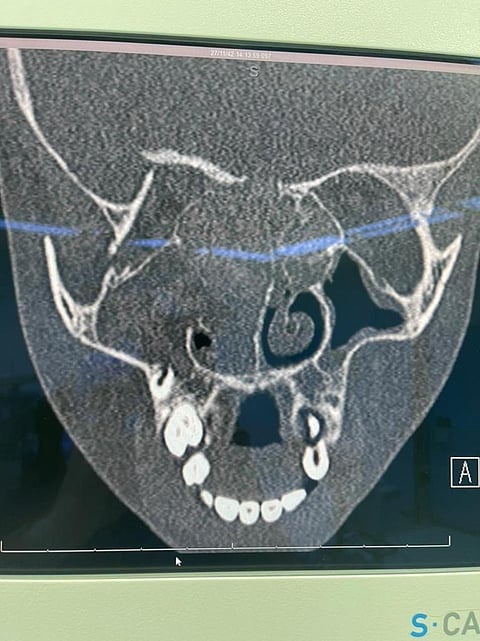

وحضرت الطفلة للمستشفى وهي تعاني من انسداد شديد في الأنف، وصداع، وبروز في منطقة العين اليمنى.. وبعد إجراء الأشعة وجميع الفحوصات اللازمة، أظهرت وجود لحميات وفطريات في الجيوب الأنفية؛ حيث كانت الفطريات ضاغطة على العين وقاع الجمجمة؛ مما دعا الفريق الطبي إلى إجراء عملية جراحية عن طريق المنظار لتنظيف الجيوب الأنفية وفتحها، في عملية استغرقت ٣ ساعات، تكللت بالنجاح والحمد لله، وتتمتع الطفلة حاليًا بوضع مستقر وتم خروجها من المستشفى بكامل صحتها.